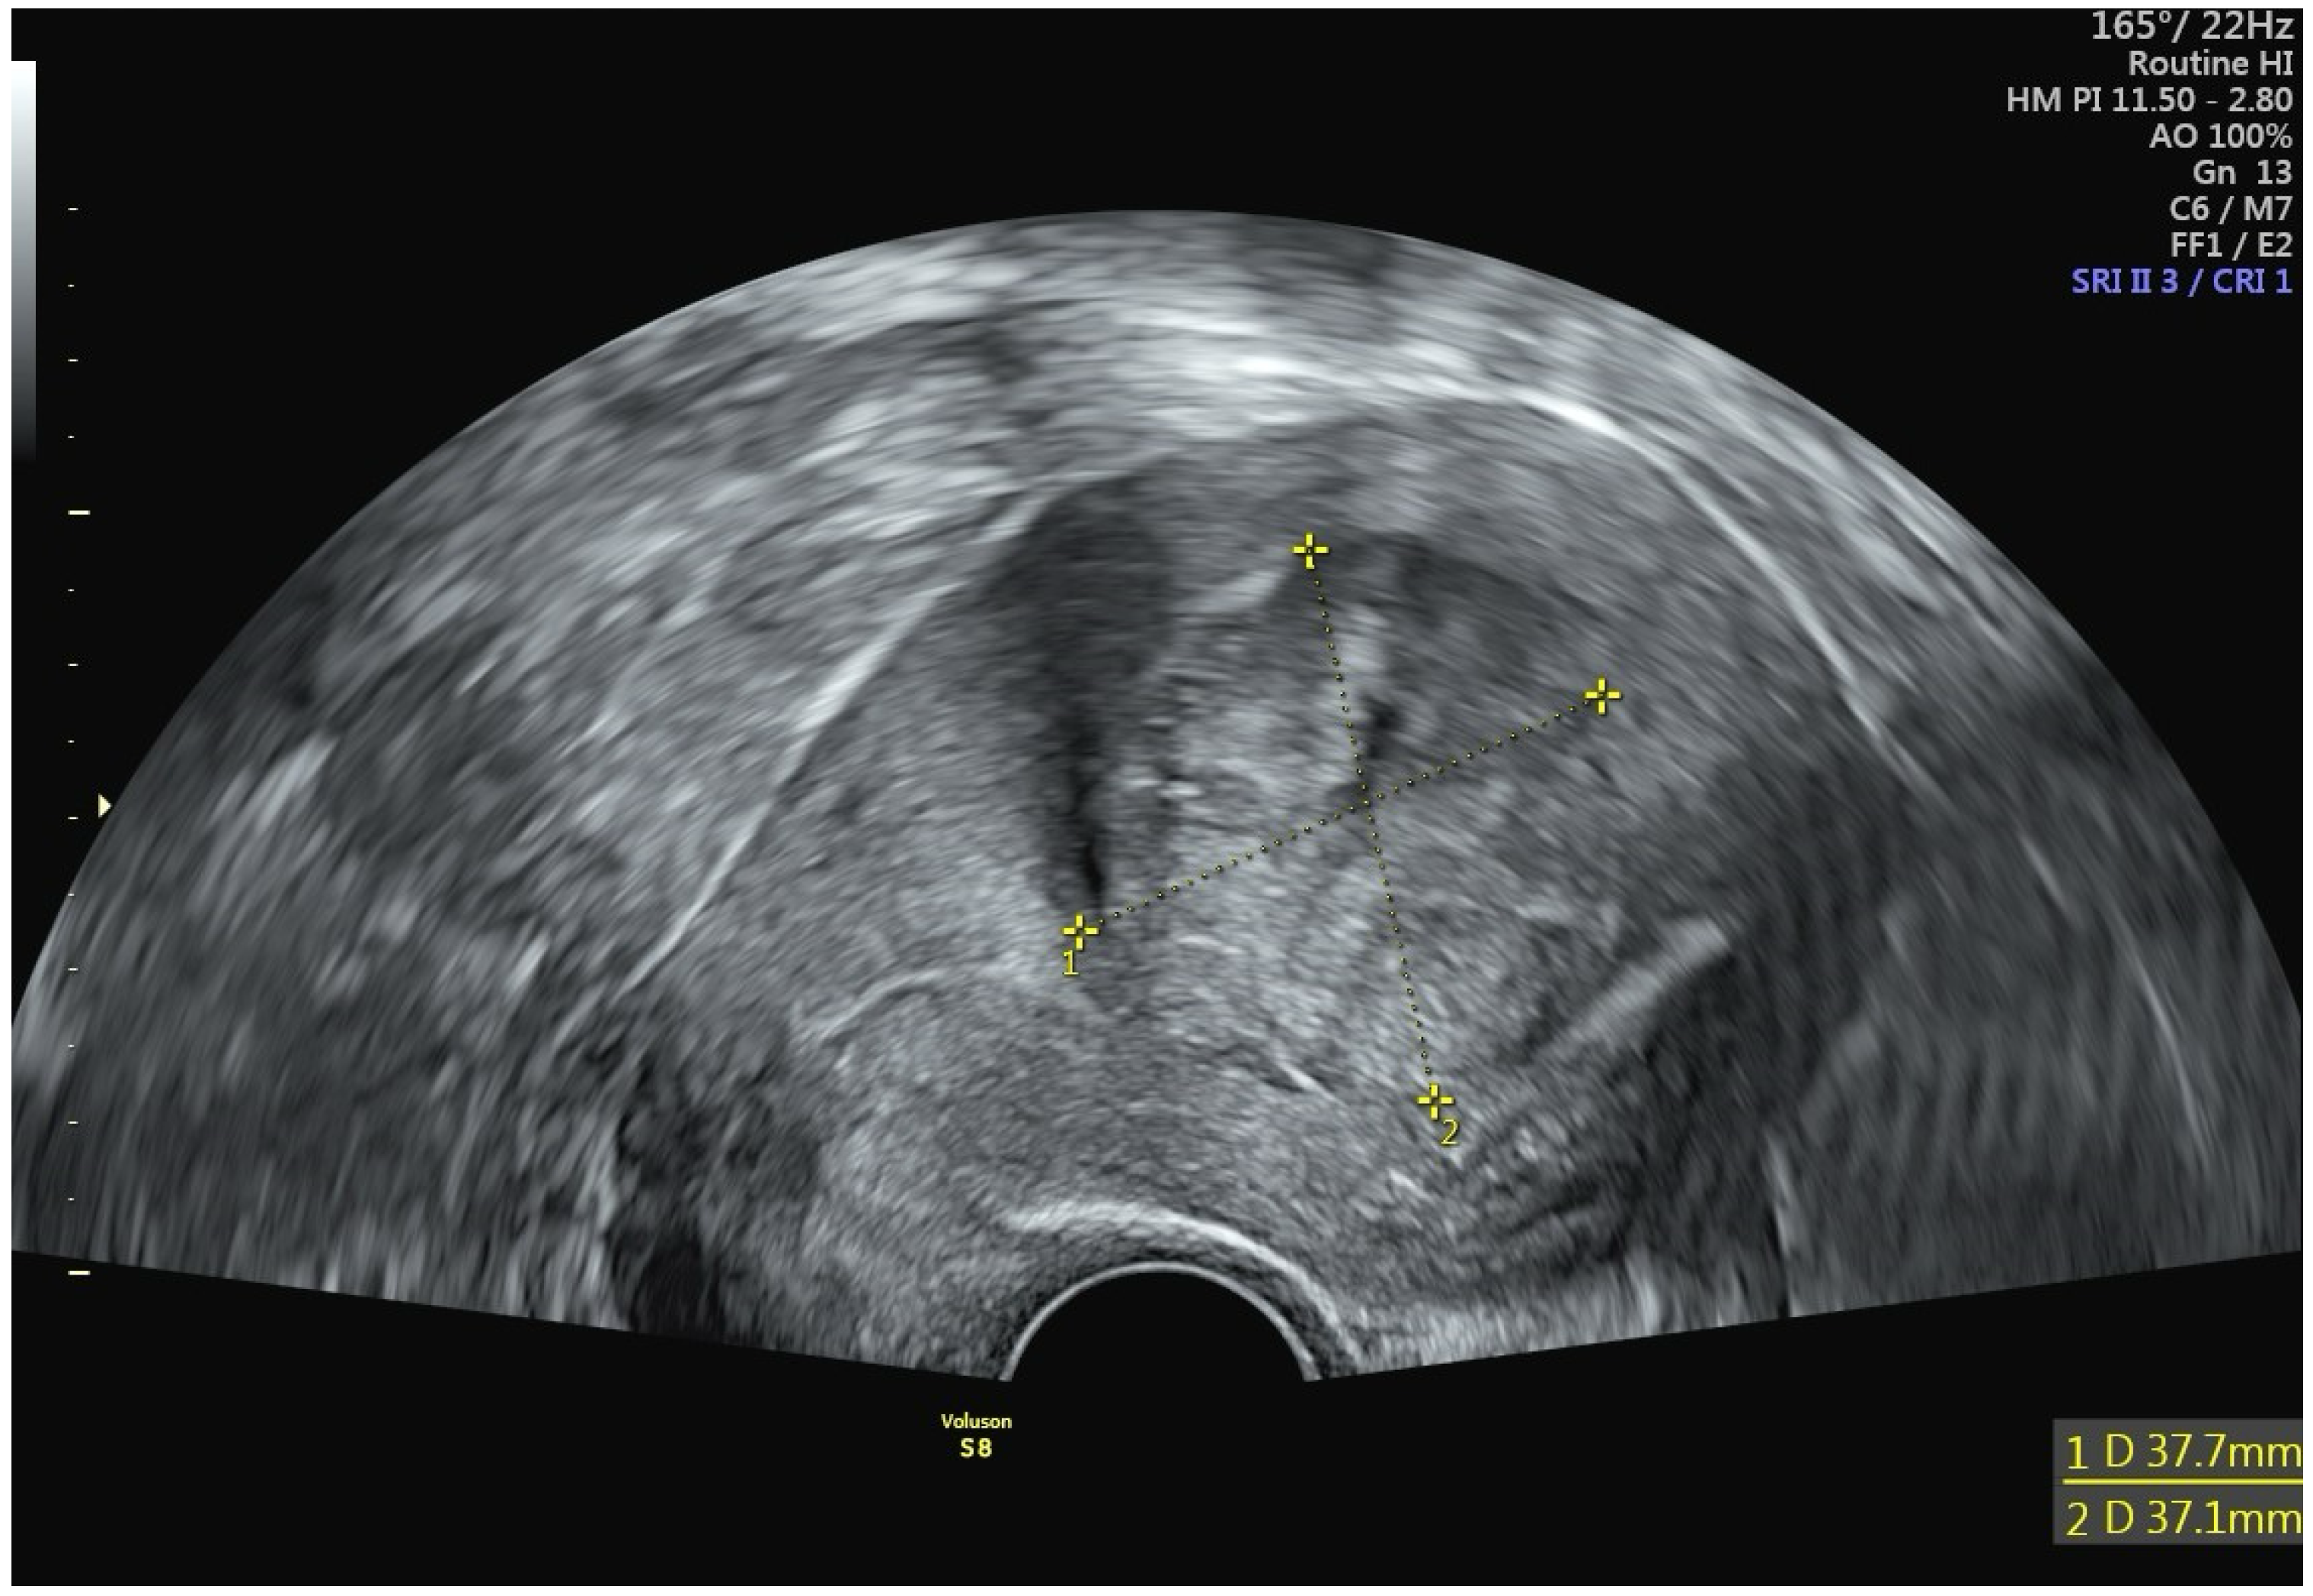

A 42-year-old woman presented at a clinic in Switzerland with a chief complaint of heavy menstrual bleeding for more than one year. She had an established diagnosis of uterine fibroids, most notably an International Federation of Gynecology and Obstetrics (FIGO) type 2 submucous fibroid that was first diagnosed 4 years earlier. At the time of that original fibroid diagnosis, the myoma had measured 2.7 cm, but in the interim had increased in size to 3.8 cm (Figure 2). Perfusion on color Doppler was increased and was centrally located (Figure 3). The patient had been suffering from heavy menstrual bleeding for over a year and wished to preserve her fertility. Thus, a combination of transvaginal fibroid resectoscopy and transcervical fibroid ablation (TFA) with the Sonata System was chosen.

Figure 2. Transvaginal sonogram revealing a 3.8 cm FIGO type 2 myoma.